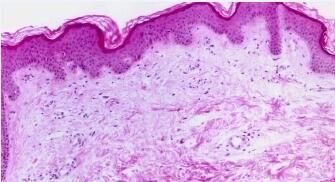

慢性荨麻疹目前是一种比较多见的皮肤病。由多种因素致使皮肤粘膜血管而出现的暂时性炎性充血。除了典型的症状之外,慢性荨麻疹还有多种比较特殊的症状。那么,特殊症状的慢性荨麻疹都有哪些呢?下面就请北京京城皮肤医院为您具体的讲解一下吧。